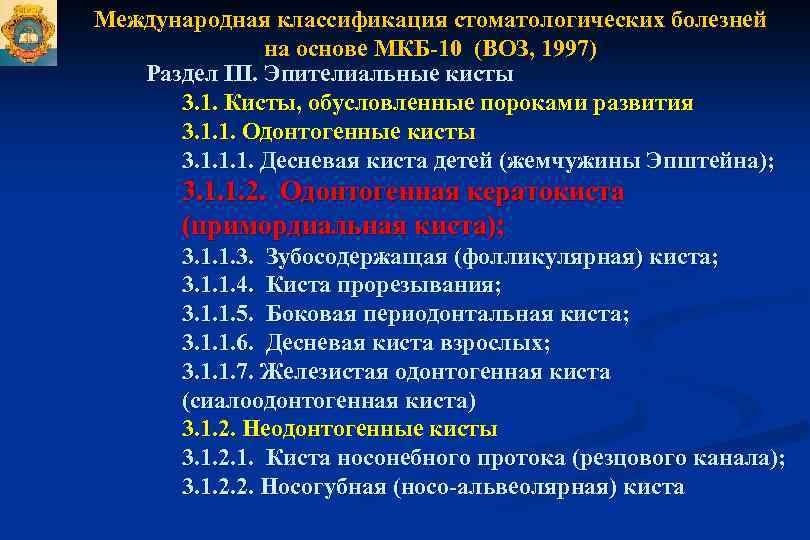

Код мкб 10 атерома головы

Код мкб 10 атерома головы 109 фото